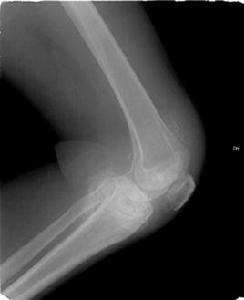

多數膝關節滑膜炎,是在上述各種膝關節損傷等情況下並發的,但也可以單獨發病或繼發於膝關節骨關節炎,後者多為老年人。在青壯年人多有急性膝關節外傷史,傷後膝關節開始發生輕度水腫、疼痛、活動受限及跛行。通常在傷後6---8小時出現滑膜反應性積液,膝關節明顯腫脹、發熱,不敢活動。檢查發現膝關節屈伸活動受限,下蹲困難並伴有疼痛,關節周圍可有局限性壓疼點,浮髕試驗陽性。慢性損傷性滑膜,可能無明顯外傷史,主要表現膝關節發軟及活動受限,腫脹持續不退,不敢下蹲。活動增多時加重,休息後減輕。久病者,可捫到膝關節囊肥厚感。